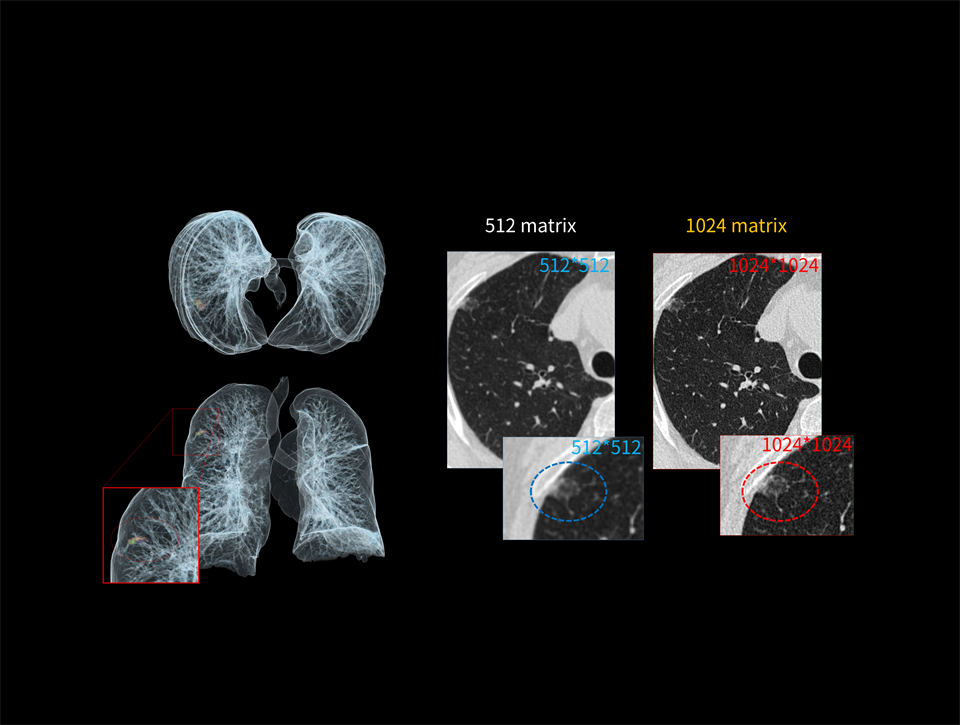

Pixeli de 0,5 mm

Cu o dimensiune a pixelului detectorului de 0,5 mm, structurile fine pot fi vizualizate mult mai clar la fiecare scanare. Îmbunătățirea rezoluției pe axa Z contribuie la reducerea efectelor de volum parțial și la creșterea capacității de a identifica leziunile suprapuse.

Matrice de reconstrucție 1024 x 1024

O matrice de reconstrucție 1024 x 1024 îmbunătățește rezoluția spațială și permite evidențierea celor mai fine detalii, chiar și în cadrul celor mai dificile examinări.

Matricea de reconstrucție de înaltă definiție evidențiază nodulii de dimensiuni reduse.